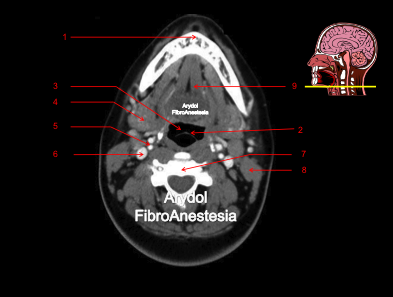

CORTE A NIVEL DEL BORDE LIBRE DE LA EPÍGLOTIS

1.mandíbula; 2.borde libre de la epíglotis; 3. vallécula derecha; 4.glándula submaxilar; 5.arteria carótida bifurcada (interna y externa); 6.vena yugular interna; 7.cuerpo vertebral; 8.músculo esternocleidomastoideo; 9.músculos suelo de la boca